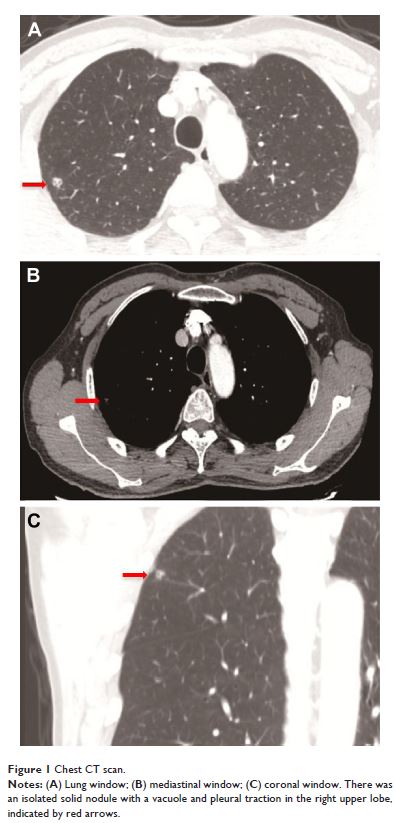

肺淋巴管肌瘤病一例报道并文献回顾